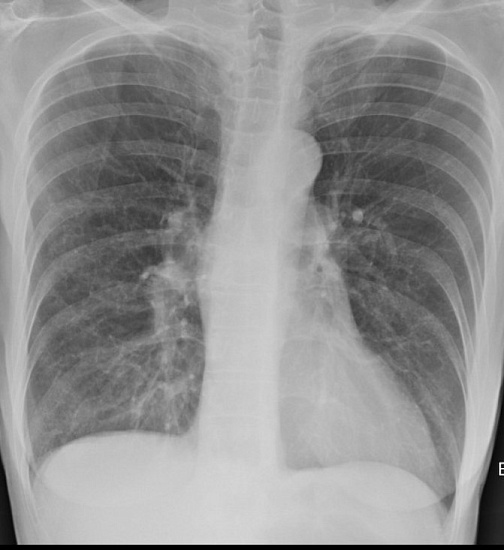

Рентгенография органов грудной клетки – распространенный метод скринингового исследования органов грудной клетки.

1. Рентгенография органов грудной клетки в 2-х проекциях - скрининговое исследование органов грудной клетки, выполняемое в двух проекциях.

2. Рентгенография легких в прямой проекции – скрининговое исследование органов грудной клетки, выполняемое в двух проекциях.

3. Прицельная рентгенография органов грудной клетки – исследование позволяет оценить наличие воспалительных, травматических, опухолевых, профессиональных (силикатоз, асбестоз) изменений легких.